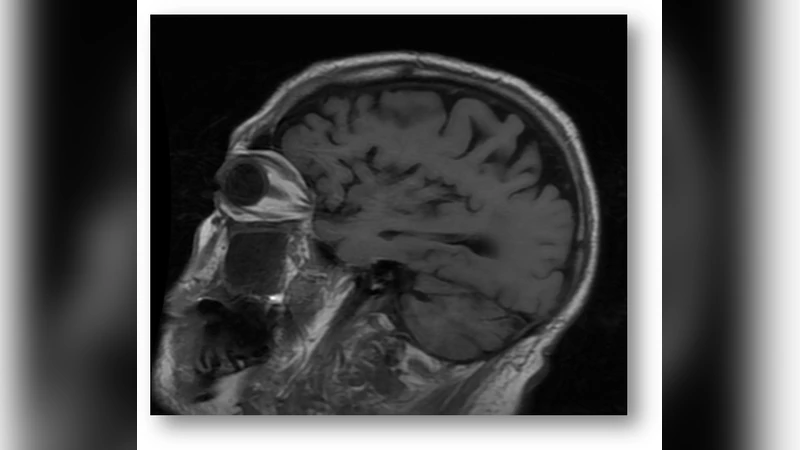

본 논문은 인공신경망(ANN)으로 구축한 인지 모델을 활용해 알츠하이머병(AD)의 동적 발생 메커니즘을 이론적으로 설명한다. 신경망의 가중치 감소, 연결 재구성, 기억 저장·소멸 과정을 AD 병리와 연관짓고, 이를 통해 질환의 진행 과정을 시뮬레이션할 수 있음을 주장한다. 실험적 검증 없이 개념적 모델링에 머무르는 점이 특징이다.

본 논문은 인공신경망(ANN)을 인간의 인지 시스템에 대한 추상적 모델로 삼아 알츠하이머병(AD)의 발생 메커니즘을 설명하려는 시도를 보인다. 먼저 저자들은 기존의 ANN 구조—입력층, 은닉층, 출력층—에 시냅스 가중치의 점진적 감소와 연결 재배치를 도입한다. 이는 신경세포의 시냅스 손실 및 재구성 현상을 메타포적으로 구현한 것이다. 논문은 이러한 가중치 감소가 일정 임계값을 초과하면 네트워크 전체의 정보 전달 효율이 급격히 저하되고, 이는 기억 회복력의 급격한 감소와 동일시한다.